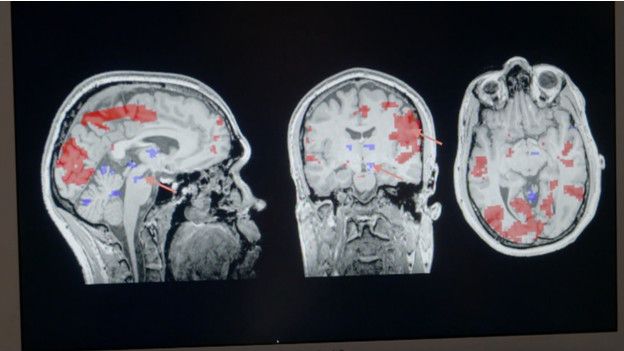

Así que me reuní con la doctora Helen Fisher, antropóloga y asesora del sitio Match.com y quien encontró un escáner cerebral para responder a esta pregunta.

Y ofrecí a mi hermano gemelo como conejillo de indias, quien se sometió a un escáner con una foto de su esposa Dinah.

Afortunadamente para todos, mostró el perfil de una persona enamorada.

Una región del cerebro llamada área tegmental ventral, relacionada con el placer y la recompensa, se mostró altamente activa. Mientras que la zona de la corteza frontal que controla el razonamiento lógico, apareció desactivada.

Este es un estado que los científicos básicamente se refieren como “amor romántico y apasionado” que no permite pensar con claridad.

Mi hermano Chris estaba, neurológicamente hablando, loco de amor.